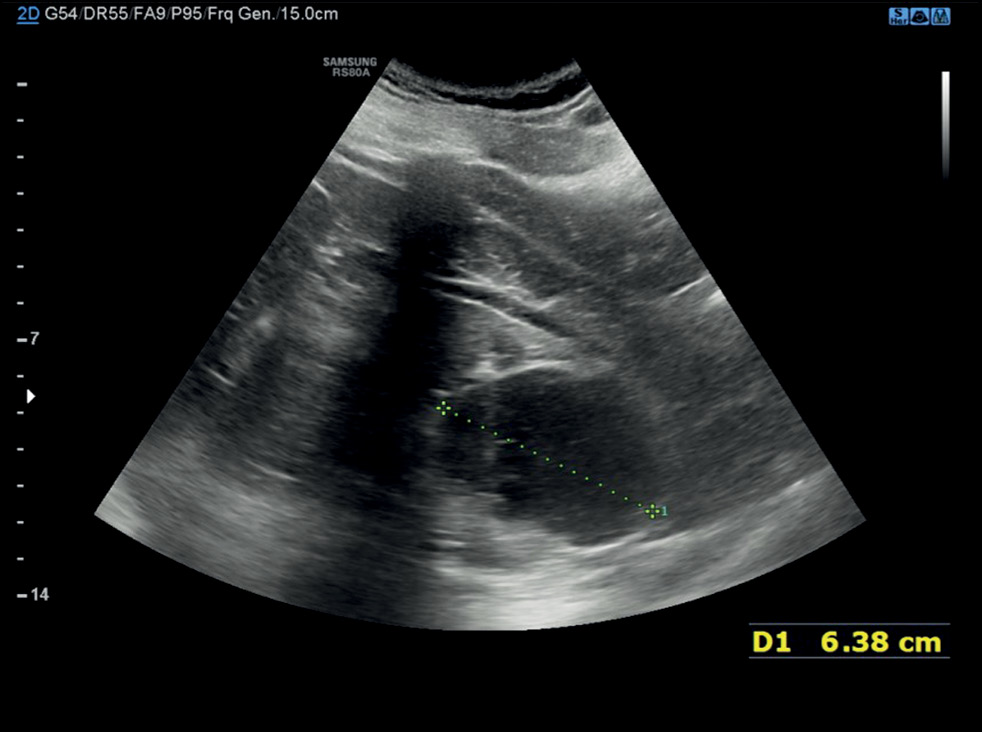

Radiological evaluation of a calyceal diverticulum presenting with hematuria

Abstract

Calyceal diverticula, also known as pyelogenic cysts, are a relatively uncommon condition, which is usually asymptomatic and incidentally diagnosed during routine imaging. In some cases, they may lead to concerning symptoms such as hematuria and flank pain, mimicking a renal tumor. In this case report, the patient suffered from hematuria that was initially suspected as a renal malignancy but was ultimately attributed to a calyceal diverticulum. The presented case allows evaluating one of the rarest and underestimated causes of hematuria and describes the main imaging features of calyceal diverticula. In particular, ultrasonography, computed tomography urography, dual-energy computed tomography, and magnetic resonance urography were performed. Subsequently, this case report also serves an educational purpose.